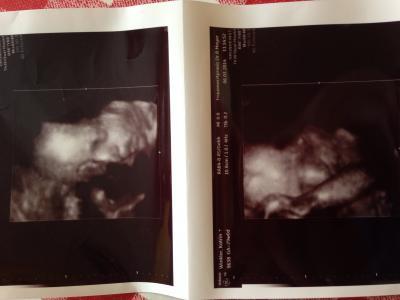

So heute war Termin zum 3 screening;) alles ist in Ordnung Beim CTG war die kleine Bauchbewohnerin, jedoch sehr aktiv. Genauso wie 1 stunde später beim US. Hab aber endlich ein 3 d Bild bekommen Gewicht ca. 1300 Gramm und 40 cm groß ;)

Bild zu Zurück vom FA - Forum für Mai - Mamis

Das freut mich und das Bild ist echt toll :) Lg channii

Bild ist schon toll, hat halt immer die Hand vorm Gesicht ;) Und sie liegt auch schon richtig, hoffe das bleibt auch so ;)

Auf das Bild bin ich neidisch. Meine Ärztin hat so ein scheiß Gerät das sie das Gesicht nur auf dem Monitor schön zeigen kann. Aber ausgedruckt sieht das dann nicht schön aus. Die Werte sind sehr schön